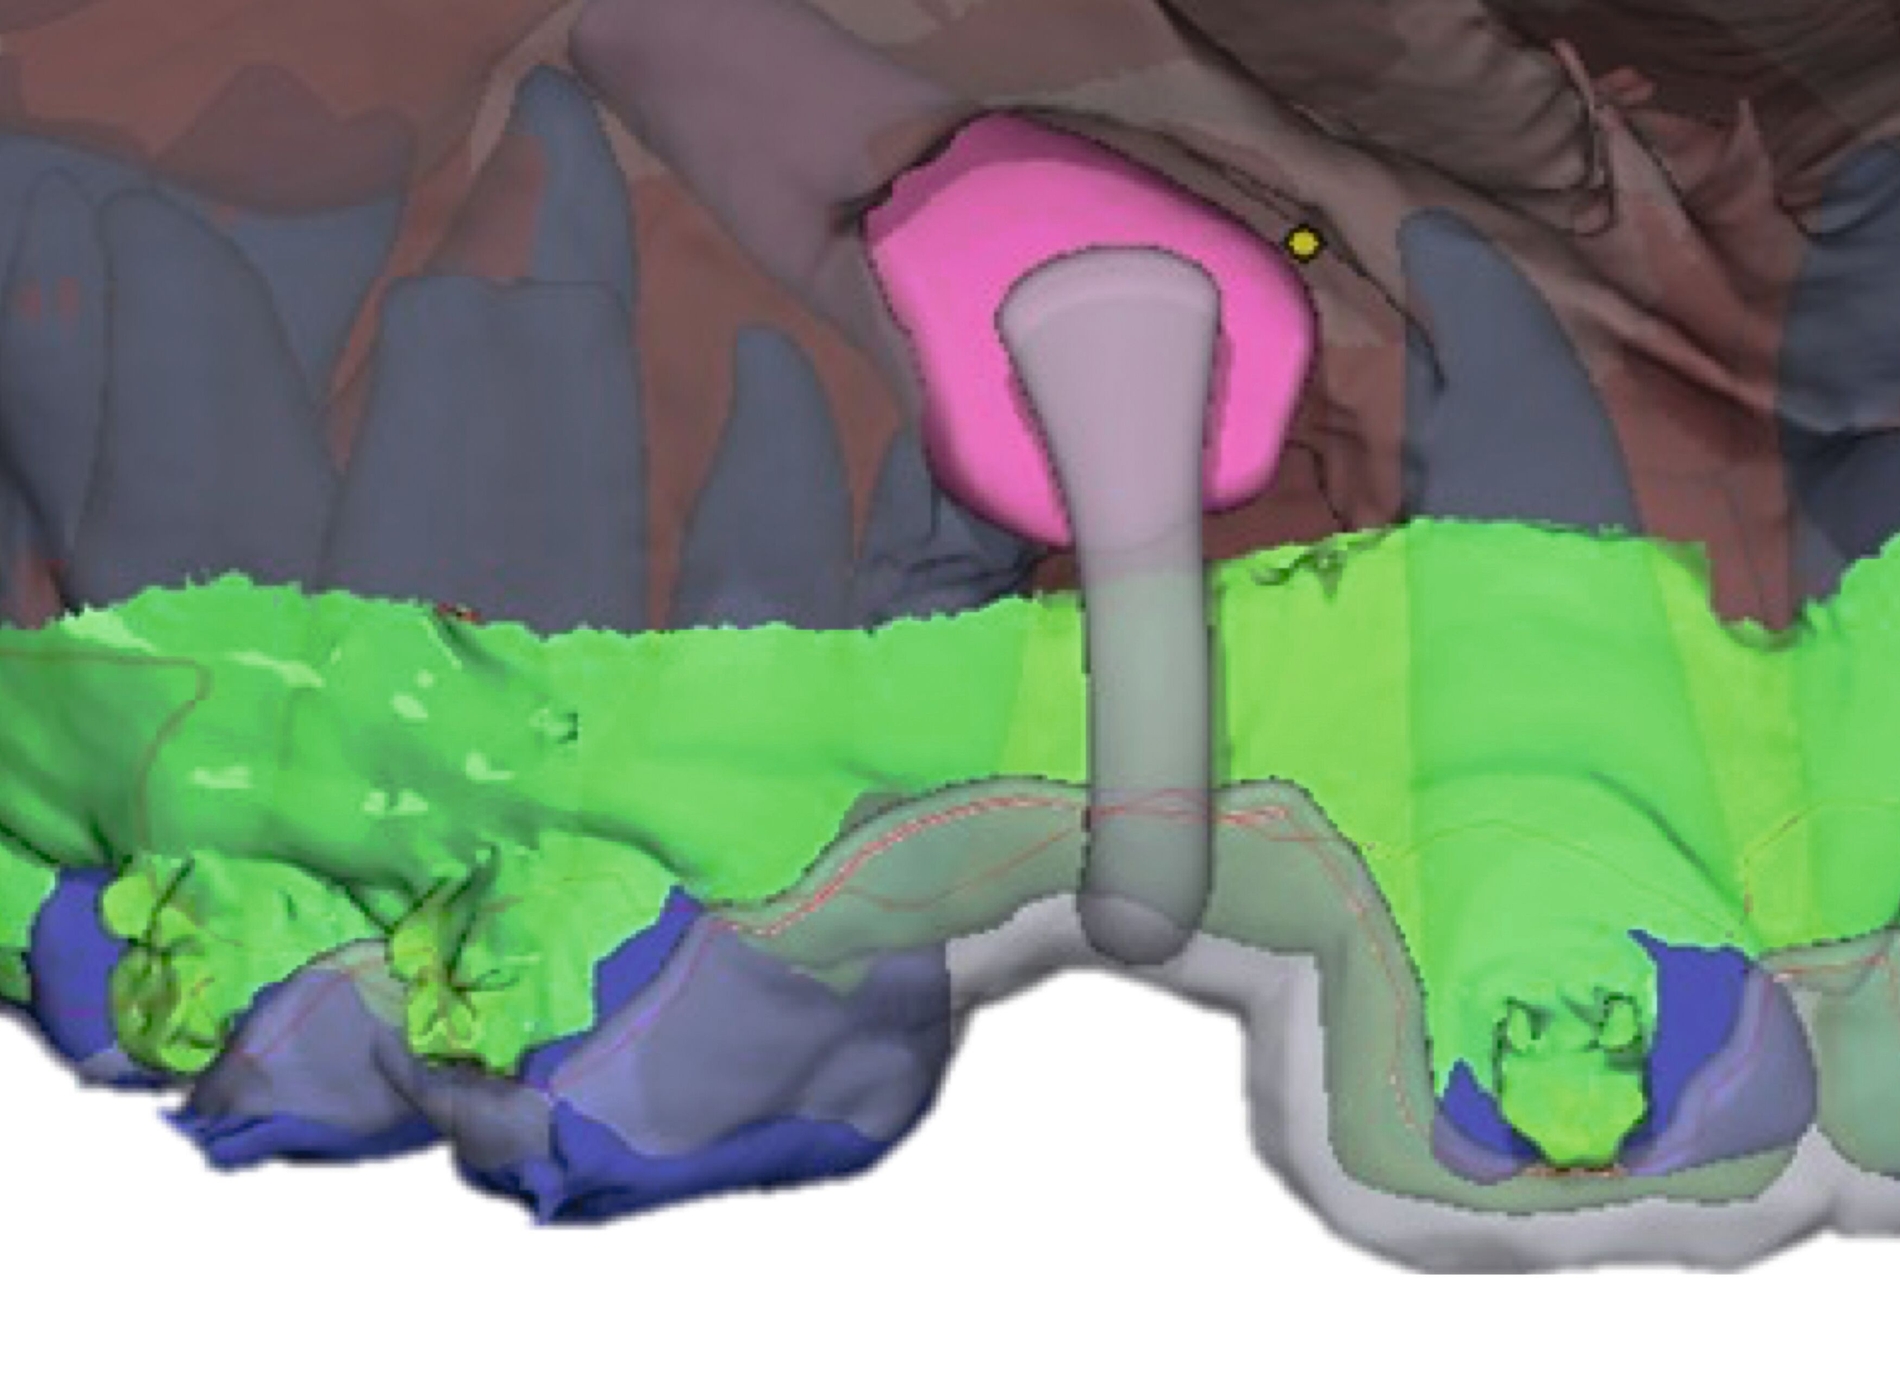

Weiter erlauben hochindividuelle 3-D-gedruckte Designs die Therapie von skelettalen Fehlständen, beispielsweise in der Therapie defizitärer Maxillae [Pasqua et al., 2022; Bazargani et al., 2023; Ludwig et al., 2024] oder im Rahmen der nonoperativen oder postoperativen Prognathie-Behandlung [Hodecker et al., 2023]. Auch die Umsetzung skelettal verankerter Apparaturen mittels nichtmetallischer 3-D-Druckmaterialien findet in einzelnen Fällen Anwendung (Abbildung 3b). Zum Einbringen der Miniimplantate eignen sich sogenannte 3-D-gedruckte „Insertions-Guides“, die nach vorheriger digitaler Planung der Miniimplantat-Position, eine hochgenaue Insertion ermöglichen [Wilmes et al., 2022; Wilmes et al., 2022]. Die virtuelle Planung der Minischraubeninsertion ermöglicht eine sichere und nachvollziehbare Evaluation sämtlicher relevanter Gewebe, um die ohnehin geringen Risiken weiter zu minimieren. Zusätzlich kann man die Biomechanik der digital geplanten kieferorthopädischen Apparatur ideal koordinieren und – wenn man möchte – die Minischrauben und die Apparatur in einer Sitzung einsetzen.

Weitere Beispiele beinhalten hochkomplexe Behandlungsfälle multipler Zahnanlagen. Während die Extraktionsentscheidung und Absprache mit dem/der chirurgisch tätigen Kollegen/in allein auf Basis der Bildgebung oft limitiert ist, erleichtern 3-D-gedruckte Modelle des segmentierten DVTs sowohl die Entscheidung als auch die Absprache und ermöglichen darüber hinaus eine genauere Planung des chirurgischen Vorgehens (Abbildung 6c). Gleiches betrifft parodontalchirurgische Eingriffe, in denen sogenannte „Cutting guides“ eine zuvor digital geplante Gingivektomie ermöglichen (Abbildung 6d). Im Bereich der Freilegung verlagerter Zähne können Schablonen dem/die chirurgisch tätigen Kollegen/in sowohl die Freilegung des Zahnes (Abbildung 6e) als auch die Anbringung eines Attachments (Abbildung 6f) erleichtern und dabei die kieferorthopädisch gewünschte Attachmentposition passgenau übertragen.